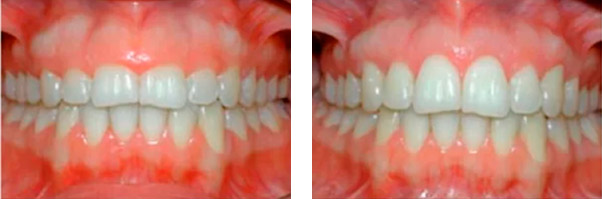

FACETAS E LENTES ODONTOLÓGICAS

São lâminas de porcelana que são aplicadas sobre a superfície dentária para recuperar forma, cor e textura de dentes amarelados, desalinhados e sem contorno estético.

As vantagens dessa técnica é proporcionar ao paciente tratamento mais rápido, quando comparado à outras técnicas. Além da beleza do material utilizado a superfície dentária sofre mínimos desgaste sem comprometer a saude dos dentes.